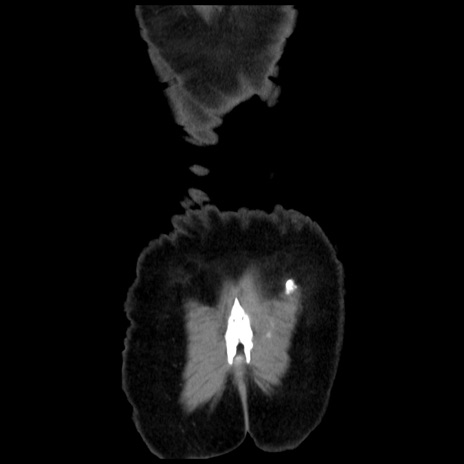

横断像

矢状断像